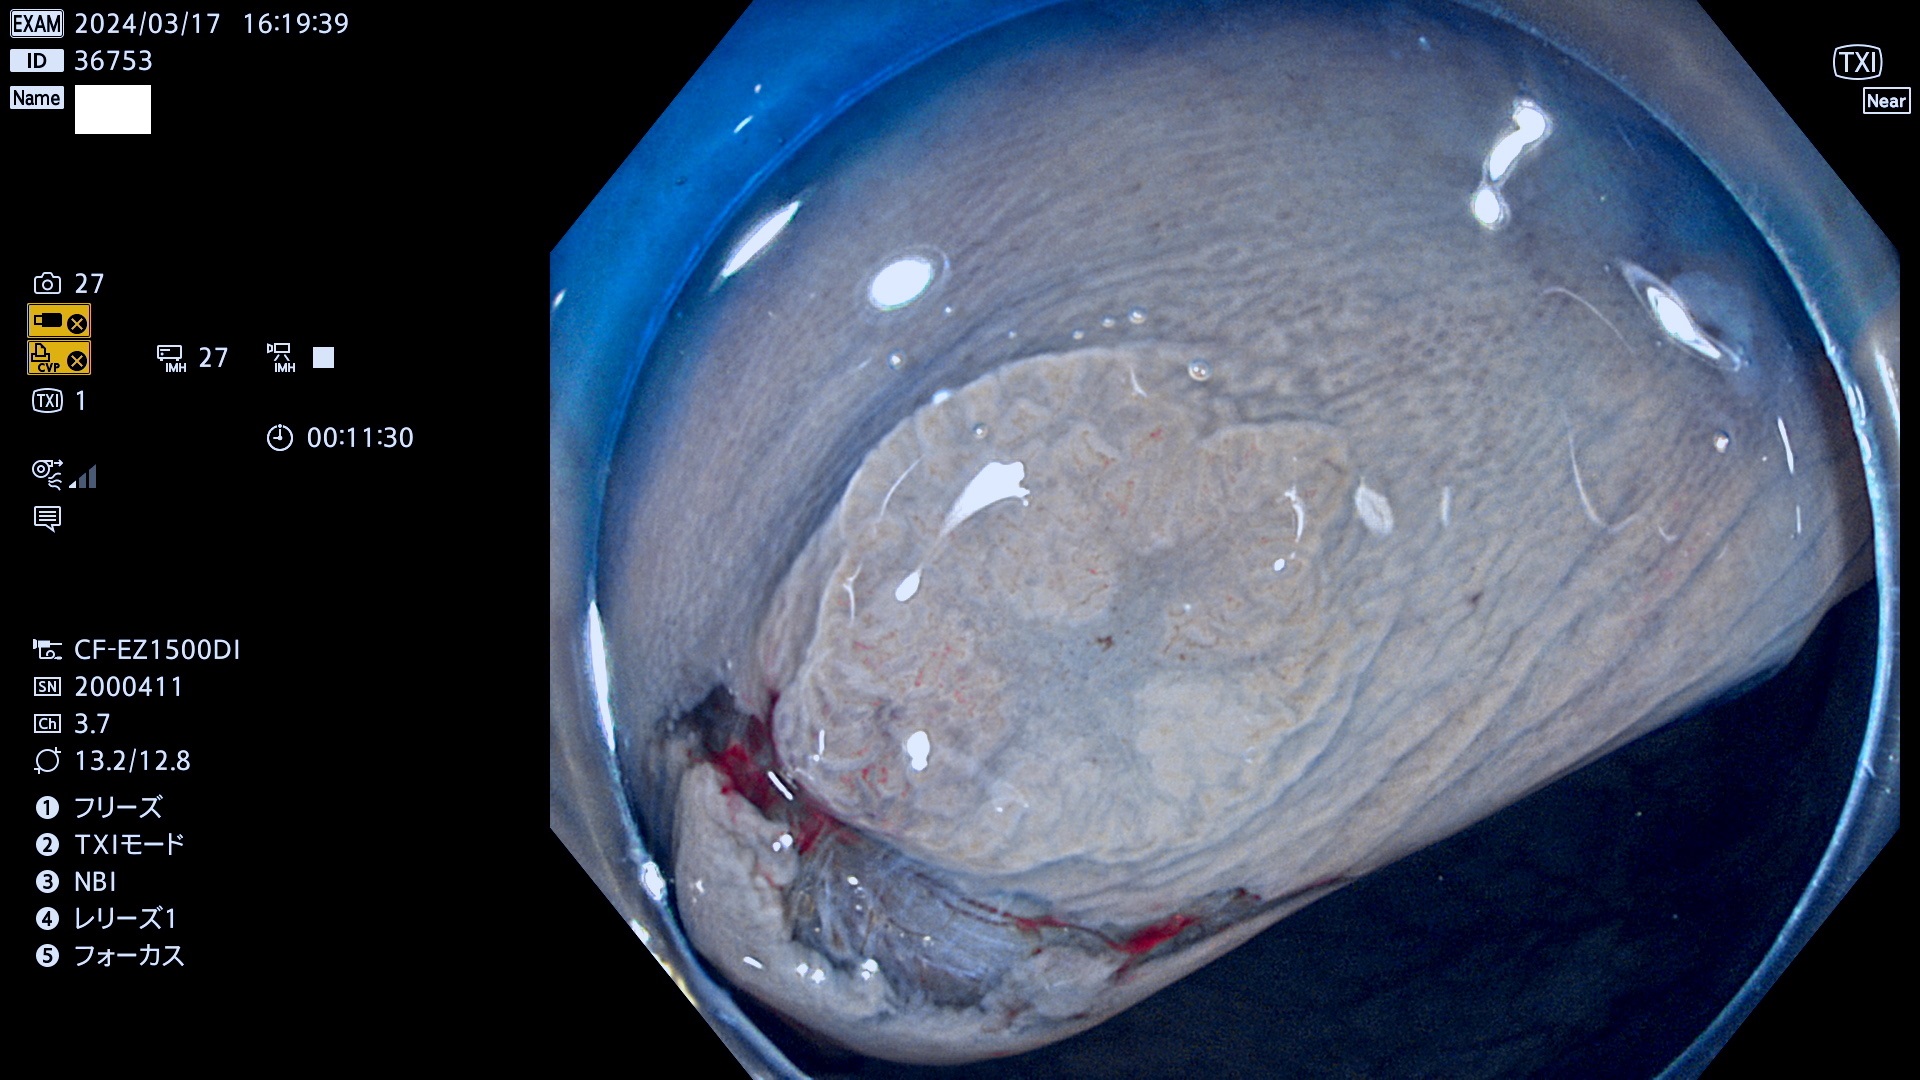

表面型腺腫(Flat Adenoma)の中で、完全に平坦な物をUb、陥凹している物をUcと呼びます。平坦隆起型(Ua)よりも、発見が難しく危険な病変です。

ビランと鑑別の困難な腺腫